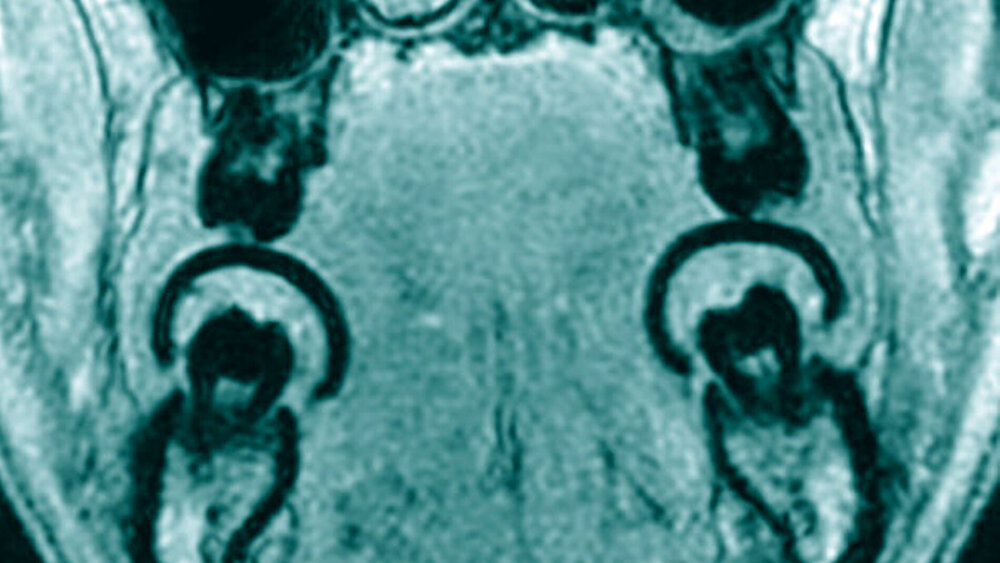

Zur Knochendarstellung eignen sich unterschiedliche MRT-Protokolle mit ihren jeweiligen Vor- und Nachteilen. Diesen Protokollen ist prinzipiell zu eigen, dass Sie kurze beziehungsweise ultrakurze Echozeiten nutzen und somit Gewebetypen wie Knochen oder Zahnhartsubstanz darstellen. Dabei sind derzeit in der klinischen Anwendung isotrope Auflösungen von 0,3 bis 0,6 mm möglich [Flügge et al., 2020; Flügge et al., 2020; Hilgenfeld et al., 2020; Probst et al., 2020] (Abbildung 1). Die MRT-Scanzeiten können aktuell bis in den Bereich von etwa drei Minuten reduziert werden [Probst et al., 2020]. Zudem existieren unterschiedliche Sequenzprotokolle, um metallische Artefakte, sogenannte Suszeptibilitätsartefakte, zu verringern [Hilgenfeld et al., 2017; Probst et al., 2017]. Als Vorbereitung für die MRT-Aufnahme werden Kunststoffschablonen beispielsweise in Tiefziehtechnik angefertigt und kurz vor der MRT-Aufnahme mit einem Material befüllt, das lokal die Kontrastierung der Zahnoberflächen verbessert. Im Anschluss werden die Schablonen mit dem kontrastierenden Material während der MRT-Aufnahme getragen [Hilgenfeld et al., 2019; Probst et al., 2020].

Anschließend kann die Implantatpositionierung entsprechend den prothetischen Anforderungen, dem sogenannten „Backward Planning“, und unter Berücksichtigung der anatomischen Situation festgelegt werden (Abbildung 3). In der Seitenzahnregion des Unterkiefers kann im Gegensatz zur DVT der Verlauf des Nerven-Gefäßbündels (Nervus alveolaris inferior) eindeutig und direkt visualisiert werden [Probst et al., 2017; Burian et al., 2019; Probst et al., 2020], was einen gewissen Sicherheitsaspekt beinhaltet [Agbaje et al., 2017] (Abbildung 4).